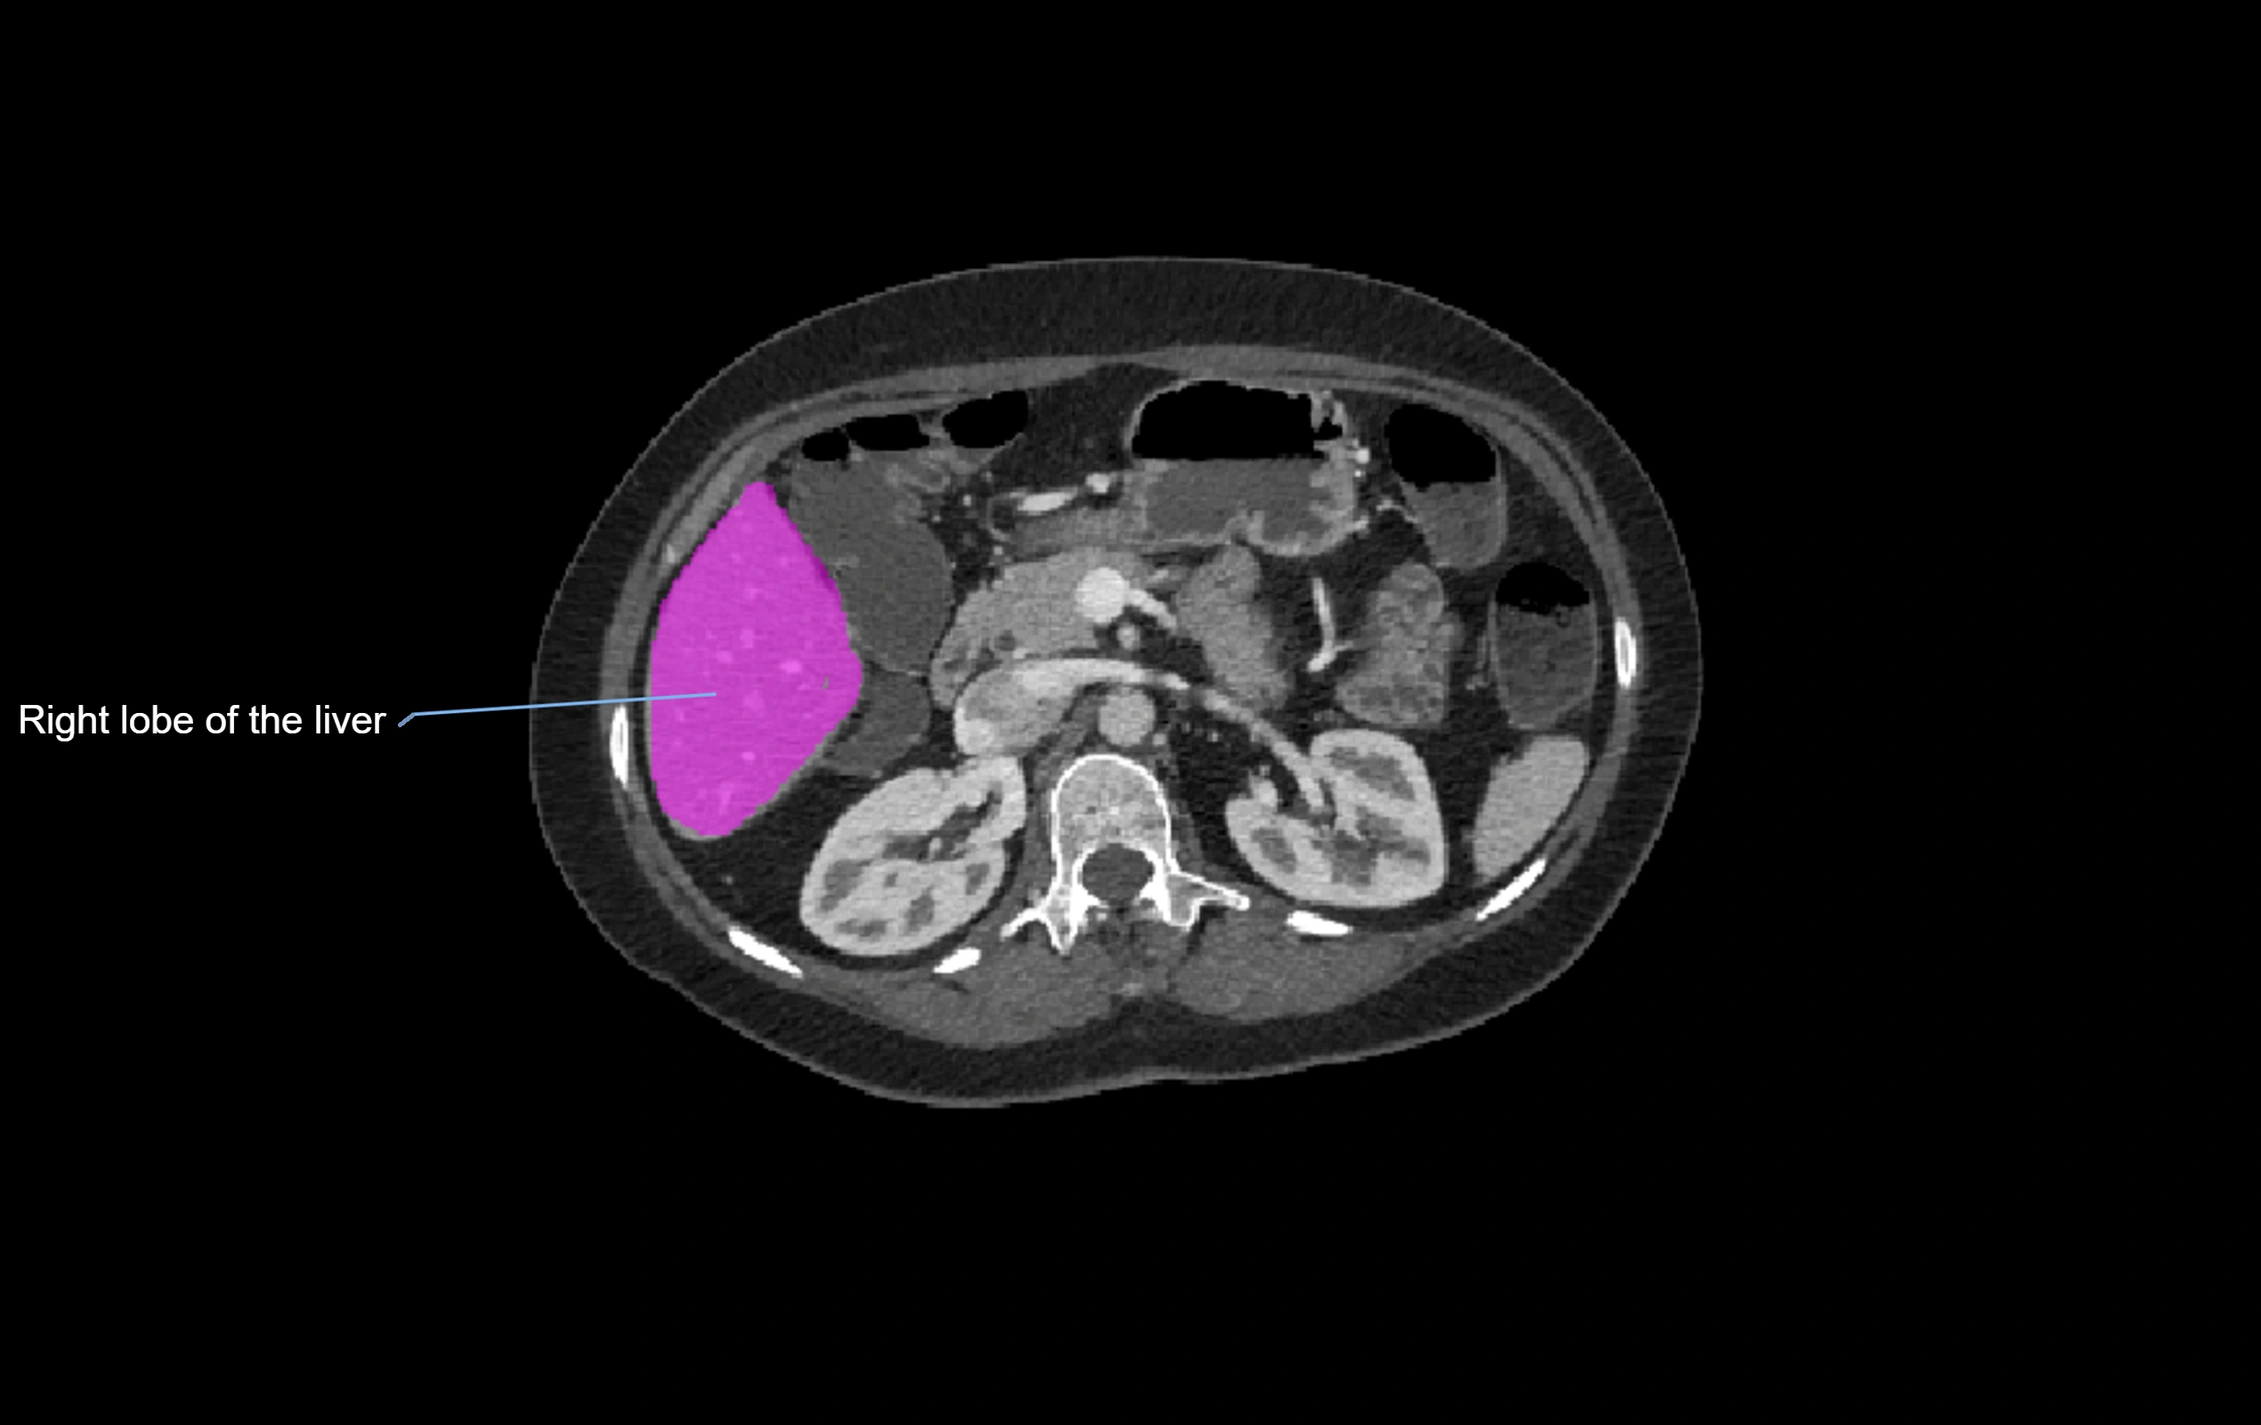

CT Pre-Contrast:

• Caudate lobe appears as a soft-tissue density, isodense to the rest of the liver

• Enlargement may be appreciated in cirrhosis or Budd–Chiari syndrome

CT Post-Contrast:

• Homogeneous enhancement in the portal venous phase, similar to rest of liver

• Independent venous drainage into the IVC may be visualized

image

CT Image